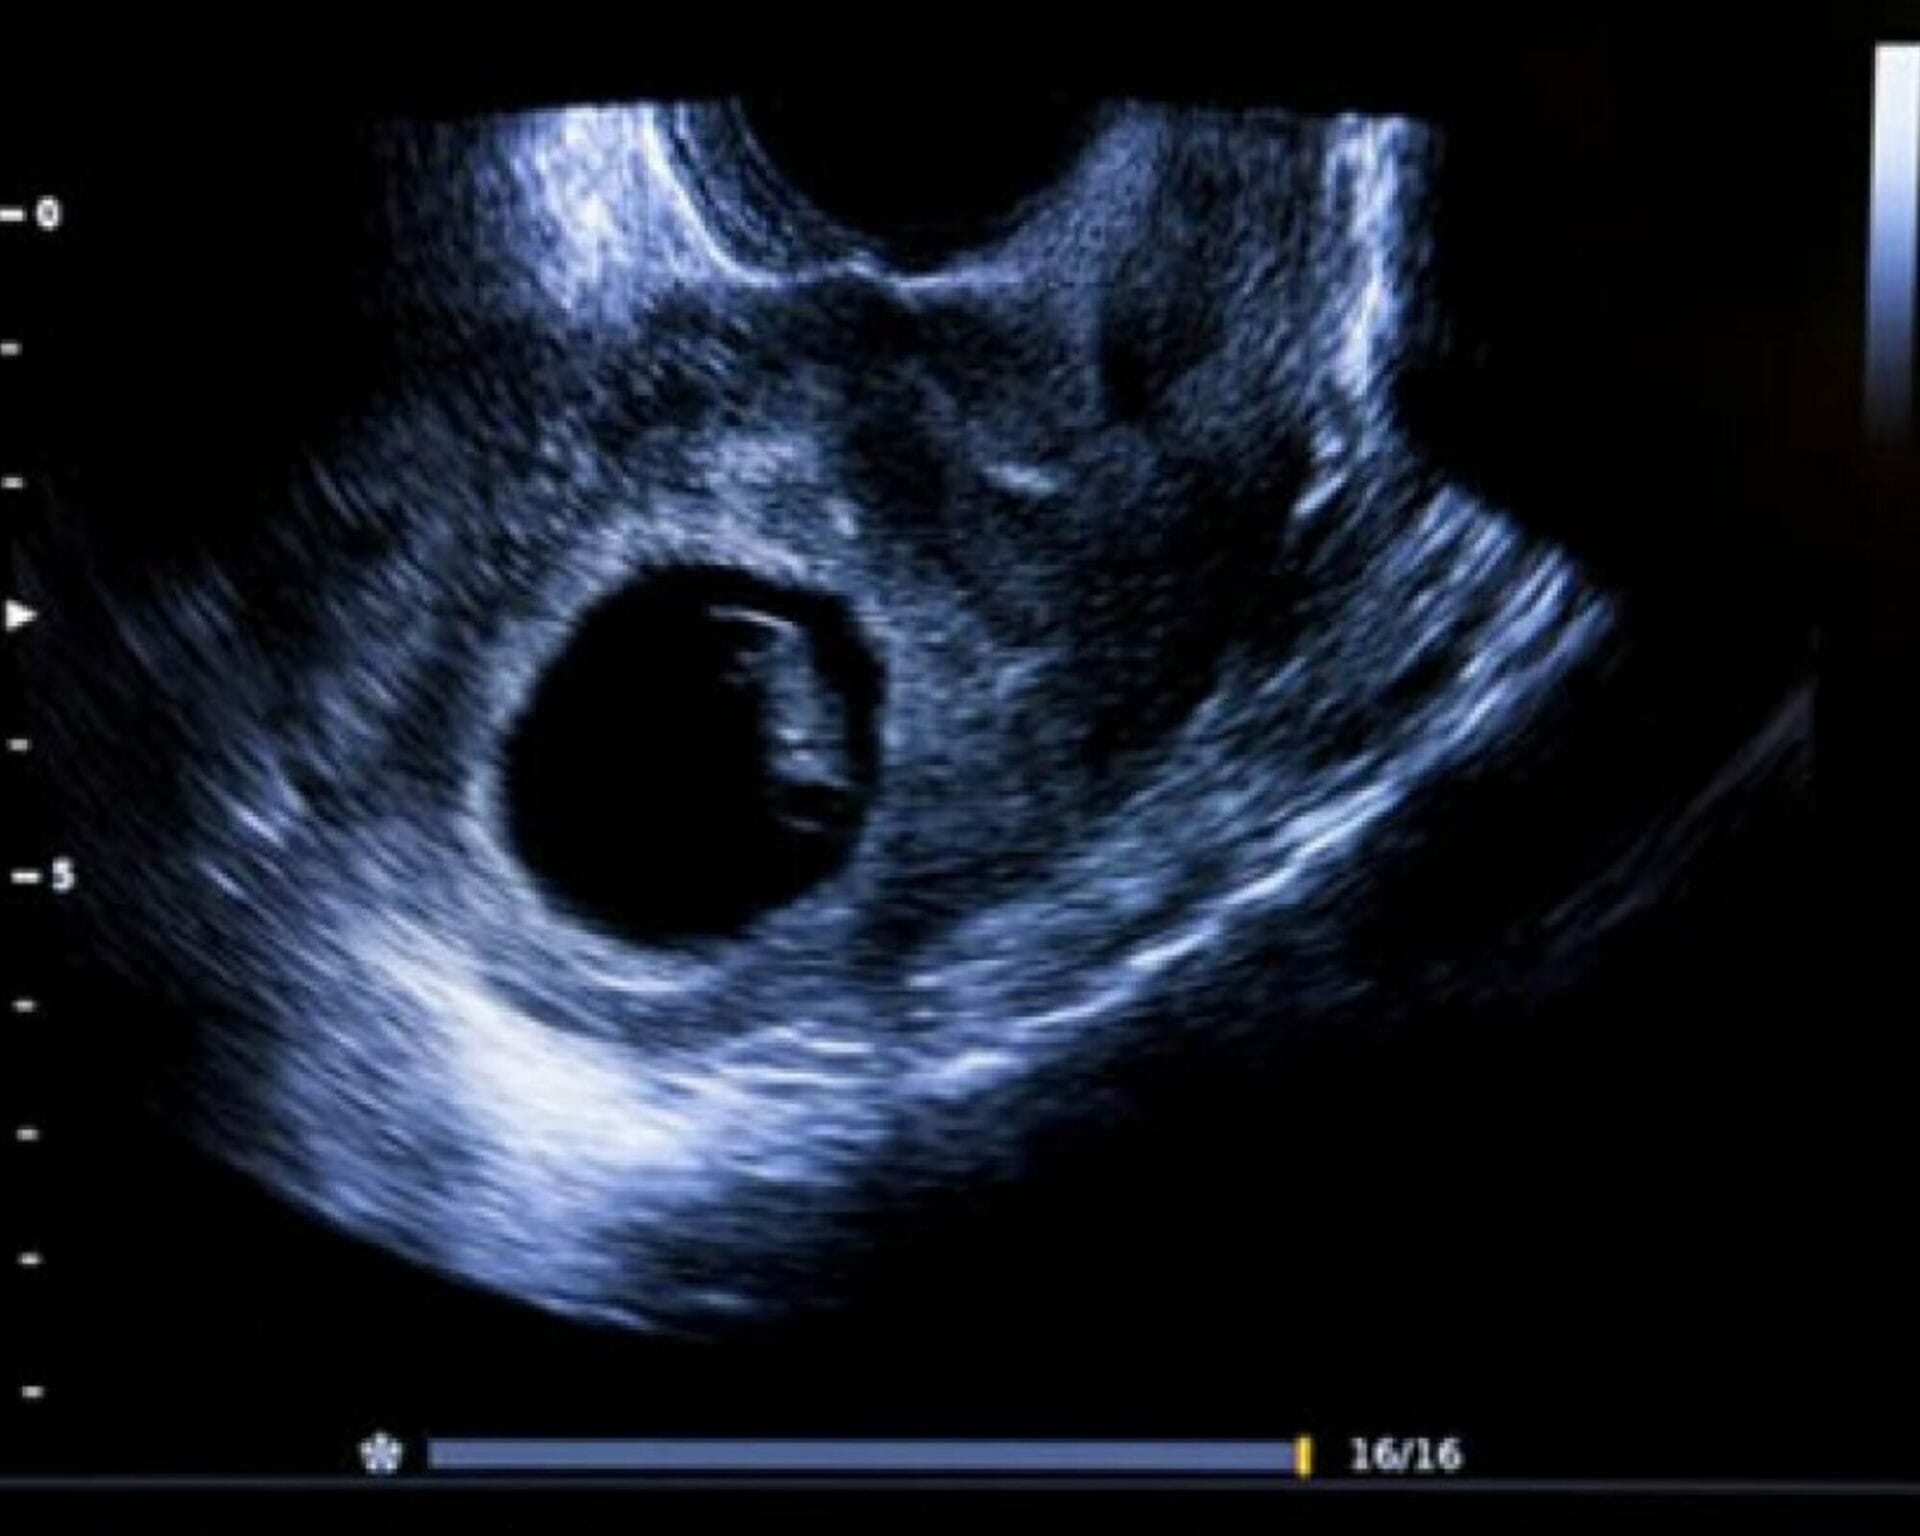

الحمل بكيس فاضي هو حالة نادرة تحدث عندما يتشكل كيس فاضي في الرحم بدون وجود جنين داخله. في هذه الحالة، يتطور الكيس الأولي (المشيمة) بشكل طبيعي، ولكن لا يتطور الجنين. يعتبر الحمل بكيس فاضي نوعًا من إجهاض المفرط، حيث أن جسم المرأة يظهر علامات حمل مثل زيادة مستوى هرمون β-hCG، لكن صورة الموجات فوق الصوتية تظهر افتقارًا لأية هيئات جنينية. قد تظهر أعراض مثل نزف وآلام شبيهة بآلام الحيض.

يشير الحمل بكيس فاضي إلى حالة نادرة تتميز بتشكل كيس فاضي في الرحم دون وجود جنين داخله. يعني ذلك أن المشيمة تتطور بشكل طبيعي، لكن لا يحدث تطور للجنين. رغم أن المرأة قد تعاني من أعراض الحمل المبكرة وزيادة مستوى هرمون β-hCG في الدم، إلا أن صورة الموجات فوق الصوتية تظهر عدم وجود جسم جنيني في الكيس. تصاحب هذه الحالة أعراض مثل نزف خفيف وآلام شبيهة بآلام الحيض. يعود التشخيص دقته إلى الفحص الطبي بالموجات فوقَ صَوتِيةٍ عفْويةٍ واختبارات من قِبَلِ مُخِتَصِّ هذا المجال. من المهم مشاركة قصَّةٍ سابقة لأى استخدامات بروجسترون أو استفاءَ بأعشاب التي رُبِمَا استَعْمِلَتْ في محاولةٍ لزيادَةِ فُرص الحمل

تظهر أعراض الحمل بكيس فاضي عادة في وقت مبكر من الحمل وتشمل نزيف خفيف أو آلام شبيهة بآلام الحيض. قد يشعر المرأة بانتفاخ في الثدي وغثيانًا خفيفًا. لدى التشخيص، يجرى فحص طبِّي لقِسْمِ الحوَضِ ومختص لفحوصات تلسك-RMI, RHA سية ل تتضمن صور الموجات فوق الصوتية العفْوية. كذلك يتم قياس مستوى هرمون β-hCG في الدم. استشارة طبيب مُخِتَصٍّ يُعَدّ ہامة جدا َetermined to reach a definitive diagnosis.